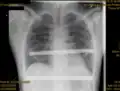

Chest x-rays are also useful in the diagnosis. The chest x-ray in pectus excavatum can show an opacity in the right lung area that can be mistaken for an infiltrate (such as that seen with pneumonia).[23] Some studies also suggest that the Haller index can be calculated based on chest x-ray as opposed to CT scanning in individuals who have no limitation in their function.[24]